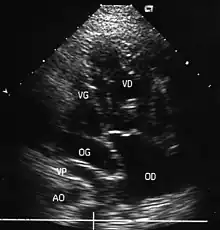

- L'échocardiographie qui est de plus en plus l'examen pratiqué en première intention. Cet examen permet d'affirmer le diagnostic en montrant les anomalies anatomiques, d'apprécier le caractère plus ou moins fonctionnel des shunts cardiaques fœtaux, de rechercher d'autres anomalies associées et dans une certaine mesure d'apprécier le retentissement de la malformation.

- Les coupes échographiques les plus utiles à cette fin sont :

- la coupe parasternale gauche grand axe : elle montre que le vaisseau issu du ventricule gauche (le plus postérieur) se dirige anormalement vers l'arrière et se bifurque précocement. C'est donc le tronc pulmonaire et non l'aorte comme normalement ;

- les coupes sous costales qui montrent bien le trajet parallèle des gros vaisseaux et leur inversion.

- Cet examen permettra d'éliminer en particulier un retour veineux pulmonaire anormal total bloqué qui aurait pu rendre compte de l’hypervascularisation pulmonaire sur la radiographie des poumons.